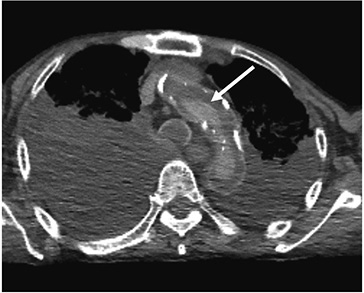

死亡時画像診断(Autopsy imaging)におけるチェックシートの